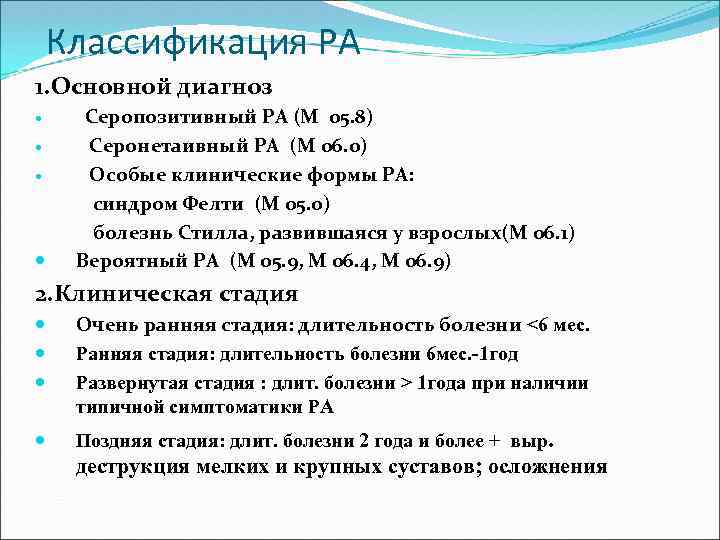

Классификация РА 1. Основной диагноз Серопозитивный РА (М 05. 8) Серонетаивный РА (М 06. 0) Особые клинические формы РА: синдром Фелти (М 05. 0) болезнь Стилла, развившаяся у взрослых(М 06. 1) Вероятный РА (М 05. 9, М о 6. 4, М 06. 9) 2. Клиническая стадия Очень ранняя стадия: длительность болезни <6 мес. Ранняя стадия: длительность болезни 6 мес. -1 год Развернутая стадия : длит. болезни > 1 года при наличии типичной симптоматики РА Поздняя стадия: длит. болезни 2 года и более + выр. деструкция мелких и крупных суставов; осложнения

Классификация РА 1. Основной диагноз Серопозитивный РА (М 05. 8) Серонетаивный РА (М 06. 0) Особые клинические формы РА: синдром Фелти (М 05. 0) болезнь Стилла, развившаяся у взрослых(М 06. 1) Вероятный РА (М 05. 9, М о 6. 4, М 06. 9) 2. Клиническая стадия Очень ранняя стадия: длительность болезни <6 мес. Ранняя стадия: длительность болезни 6 мес. -1 год Развернутая стадия : длит. болезни > 1 года при наличии типичной симптоматики РА Поздняя стадия: длит. болезни 2 года и более + выр. деструкция мелких и крупных суставов; осложнения